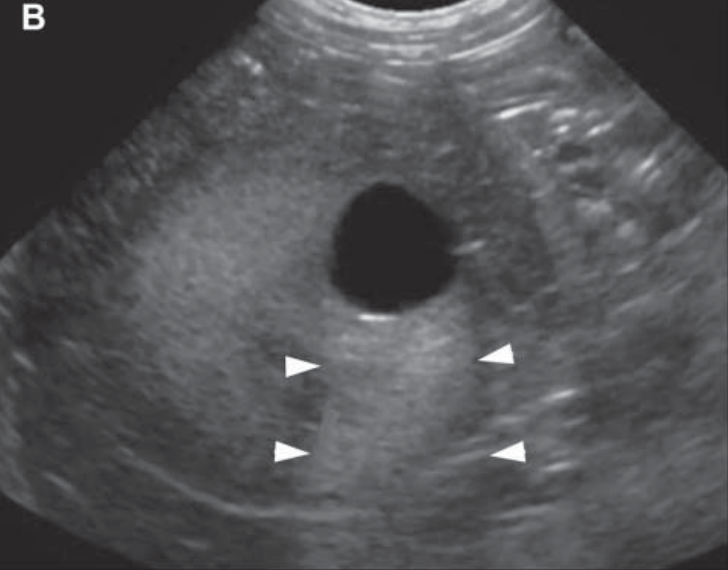

Name this artifact.

What is the cause of the artifact?

Reverberation: Occurs at highly reflective surfaces (e.g., tissue-gas interface). Some echoes are reflected back and forth between gas and transducer, then interpreted to exist at twice the depth of the original interface.